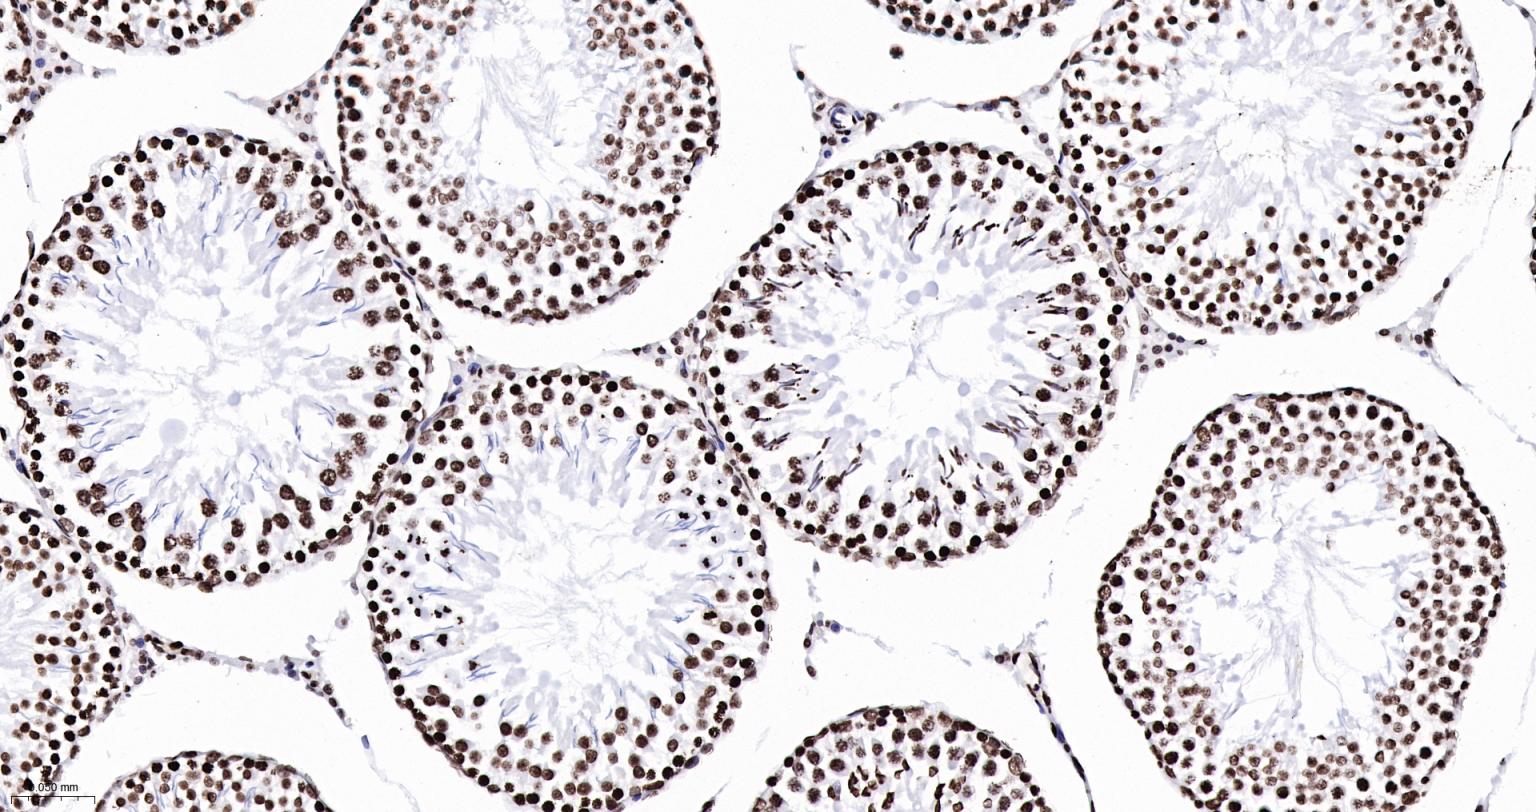

Paraformaldehyde-fixed, paraffin embedded Mouse Testicles; Antigen retrieval by boiling in sodium citrate buffer (pH6.0) for 15 min; Antibody incubation with Histone H2A.X Monoclonal Antibody, Unconjugated(bsm-61080R) at 1:200 overnight at 4°C, followed by conjugation to the SP Kit(Rabbit, SP-0023) and DAB (C-0010) staining.

Paraformaldehyde-fixed, paraffin embedded Rat Testicles; Antigen retrieval by boiling in sodium citrate buffer (pH6.0) for 15 min; Antibody incubation with Histone H2A.X Monoclonal Antibody, Unconjugated(bsm-61080R) at 1:200 overnight at 4°C, followed by conjugation to the SP Kit(Rabbit, SP-0023) and DAB (C-0010) staining.